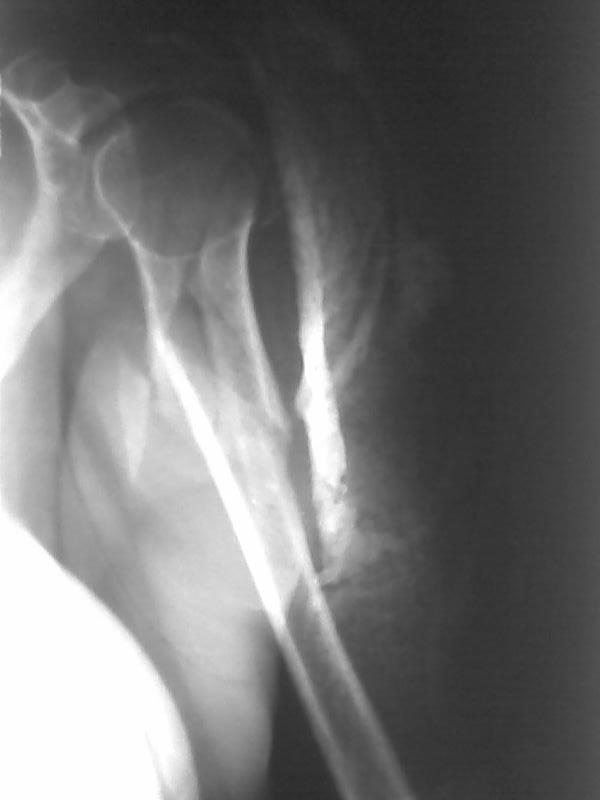

Высылаю рентгенограммы больной до операции и в гипсовой лонгете.

Сейчас больную вообщем-то особо ничего не беспокоит, незначительная

болезненность в области перелома при движениях плечом, первые два дня

была отечность кисти, которая сейчас исчезла, объем движений в

локтевом суставе постепенно увеличивается, отведение плеча пока

небольшое. Дистальное блокирование выполнено одним винтом в

передне-заднем направлении (через бицепс. Да, клинок мы конечно же

заблокировали концевым колпачком. Нас тоже беспокоит возможность

развития импиджмент синдрома, надеемся на то, что больная разработает

движения в плечевом суставе.